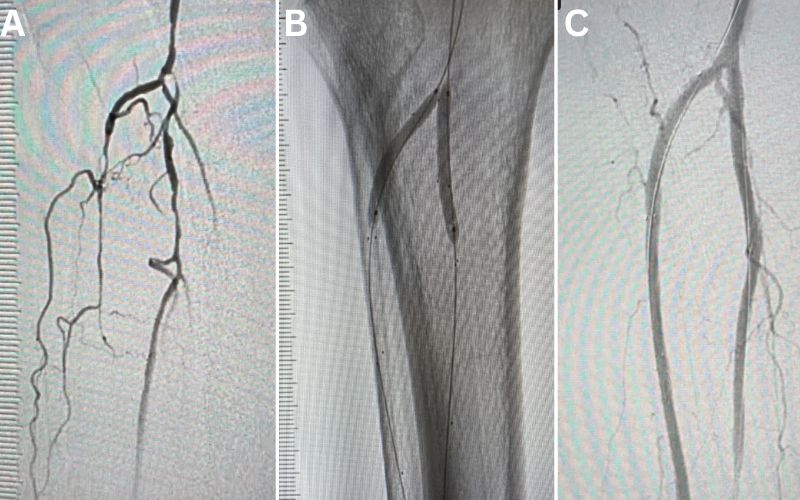

Pre-and-post angiogram photos

(A) Pre-procedural angiogram showing multifocal severe narrowing of several tibial arteries due to atherosclerotic plaque. (B) Deployment of drug-eluting resorbable scaffolds in two tibial arteries (anterior tibial and peroneal arteries). (C) Post-procedural completion angiogram showing restoration of normal tibial artery lumen with bioresorbable scaffold.